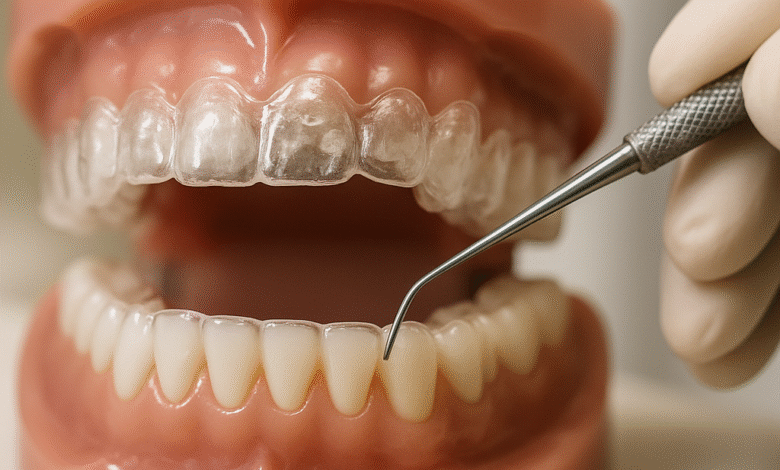

Invisalign is a modern orthodontic treatment that utilizes clear aligners to straighten teeth. Unlike traditional metal braces, these aligners are virtually invisible and can be easily removed, making them a popular choice among teens and adults alike.

- Material Quality: Invisalign aligners are made from a patented thermoplastic material designed for both strength and comfort. This advanced material holds up well against typical wear and tear.

- Resistance to Staining: The clear aligners are also resistant to staining, meaning they will remain clear throughout your treatment, maintaining an aesthetic appeal.